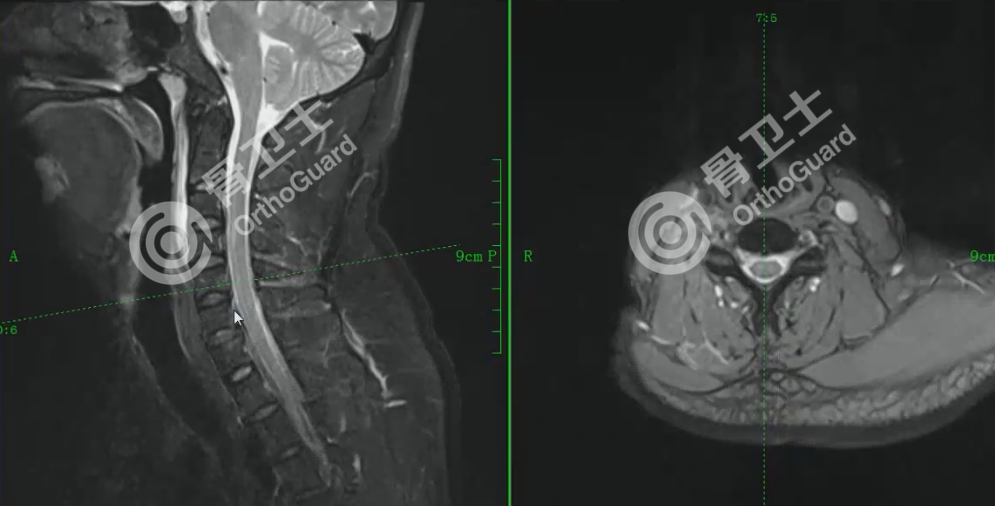

基本情况:男,38岁,因“摔伤致右大腿疼痛、出血伴活动受限1小时”入院。诊断:右股骨中远段粉碎性开放性骨折(Gustilo Ⅲ A型),右臂丛神经损伤,下颌皮肤挫裂伤,右侧第10后肋骨折,右肺轻度挫伤,左侧输尿管多发结石伴左侧肾盂及左侧输尿管上段轻度积水。治疗经过:伤口清创,复位股骨髁骨折端并行克氏针临时固定股骨髁骨折,右股骨远端外侧钢板置入,自体骨植骨,石膏托外固定。

杨述华教授表示,该病例的处理非常恰当,基本达到解剖复位的标准。股骨下端开放性粉碎性骨折处理起来是非常棘手的,开放性骨折的处理中,彻底清创是预防感染的重要手段,及时清除没有活力的组织,污染的骨块要及时、彻底消毒,碎骨块不要丢弃。对于伤口较大的粉碎性骨折,建议不要在一期手术时放入较大内固定,可以选择钢丝、克氏针等方式予以临时固定,同时搭配外固定或骨外牵引是比较稳妥的方式。中山市广济医院选择的钢板置入+自体骨植骨的方式也是值得鼓励的。对于患者上肢三角肌外展功能受限,肱二头肌、前臂斜后肌功能未恢复的情况,杨述华教授认为,患者手指运动正常,但外展功能受限,臂丛神经损伤不能完全排除,建议做臂丛神经和颈神经成像检查,确定神经损伤情况。由于患者颈3-4、颈4-5、颈5-6、颈6-7都有椎间盘突出,颈椎引起的颈脊髓损伤也不能排除。此外,还需要考虑脊髓休克征,颈脊髓受到创伤后,可能发生暂时性、一过性发生功能障碍,表现出瘫痪的症状,但磁共振检查神经并没有损伤,只是暂时的功能障碍,这类患者早期可以不做手术,观察8-12个小时,如慢慢恢复功能,则说明没有手术指征,可以慢慢恢复。但杨述华教授主张积极处理神经损伤问题,而不是保守观察。